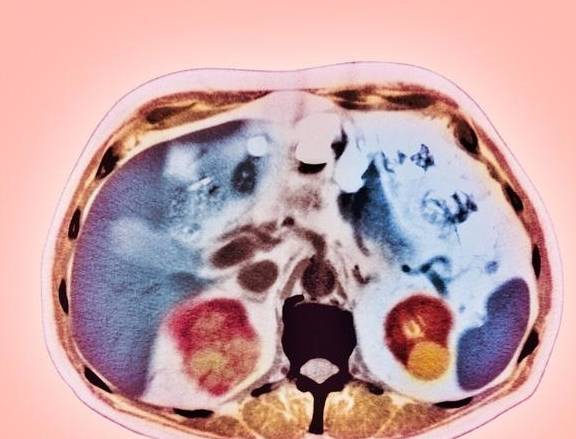

大部分肾囊肿属于良性的 , 发生恶变的可能性很小 。 一般小的肾囊肿不需做特殊治疗 , 但并不代表没有任何坏处 。 肾囊肿可持续压迫和损害肾实质或输尿管 , 从而引起肾积水 , 严重时可诱发尿毒症 。 那肾囊肿来临时会有哪些症状呢 。

文章图片